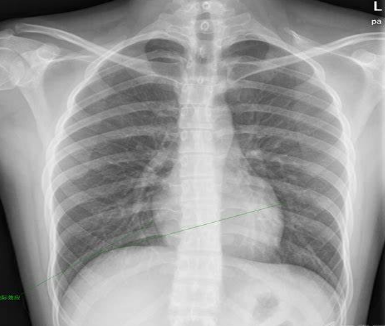

早期诊断是降低肺癌病死率的有效办法。有研究表明,低剂量螺旋CT(LDCT)的筛查阳性率为X胸片的3倍,检查出肺癌的能力为X线胸片的4倍,检查出I期肺癌能力为X线胸片的6倍。

2011年,NSLT在对美国33个医疗机构的超过5万例受试者(其中有26722人为LDCT组,26732人为胸部X光片组)进行中位随访6.5年后,发布重磅研究结果:

与胸部X光片相比,每年接受LDCT筛查的目前和曾经吸烟的肺癌高危人群,肺癌死亡率显著降低了20%(P=0.004),并且全因死亡率也降低6.7%(P=0.02)。